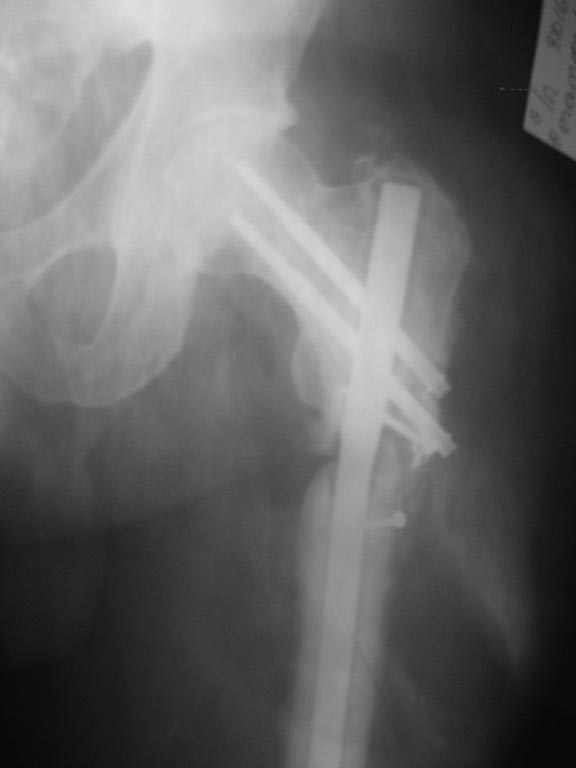

Пациенту 60 лет, после перелома бедренной кости прошло 11 мес, сахарный

диабет тип 2 субкомпенсированный, облитерирующий атеросклероз сосудов

нижних конечностей.

Первично - МОС пластиной с угловой стабильностью  с костной

аутопластикой. Через 6 мес - перелом пластины, удаление, БИОС с костной

аутопластикой. Динамизация через 8 нед после БИОС, дозированная

нагрузка. Через 12 нед  в связи с несращением - резекция концов

отломков, дистальное переблокирование с компрессией отломков, костная

аутопластика. Через 5 мес после бИОС - трансплантант  исчез, несращение.

Что  делать дальше?